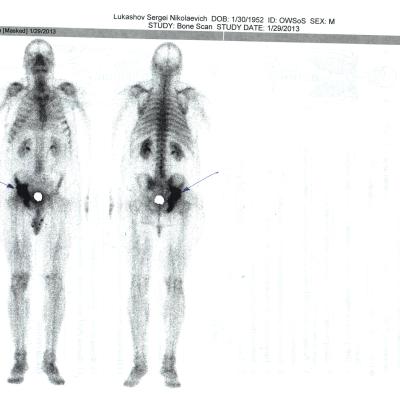

29.01.13 0стеосцинтиграфия:очаг гиперфиксации в костях таза справа.

Дз: Рак предстательной железы "T2N0M0 II ст 4 кл.гр.Метастазы в кости.